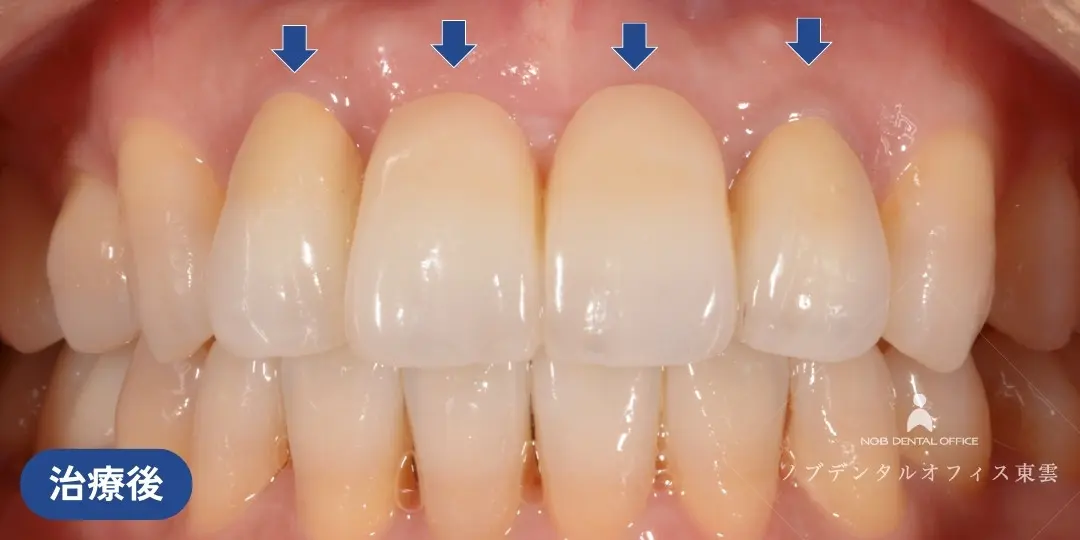

前歯の欠損を接着性ブリッジで治療した症例(60代女性)

上の前歯の歯ぐきが腫れてしまった状態を繰り返していました。

診察の結果、歯根に亀裂(きれつ)があり、残念ながら抜歯が必要との診断でした。

当院で抜歯を行いました。

インプラント・ブリッジ・入れ歯の治療計画をお話しさせていただき、治療期間やリスク、審美性や周囲の歯への負担を考慮して、接着性ブリッジで修復しました。

接着性ブリッジとは、隣の歯の一部のみを削り、貼り付けるタイプの補綴物です。

支台歯の削る量を最小限に済ませ、審美性も高いのが特徴です。

抜歯した状態。治療期間中は仮歯を入れます。

隣の歯の一部のみを削り、ジルコニアを貼り付けています。削る量が少なく負担の少ない治療です。